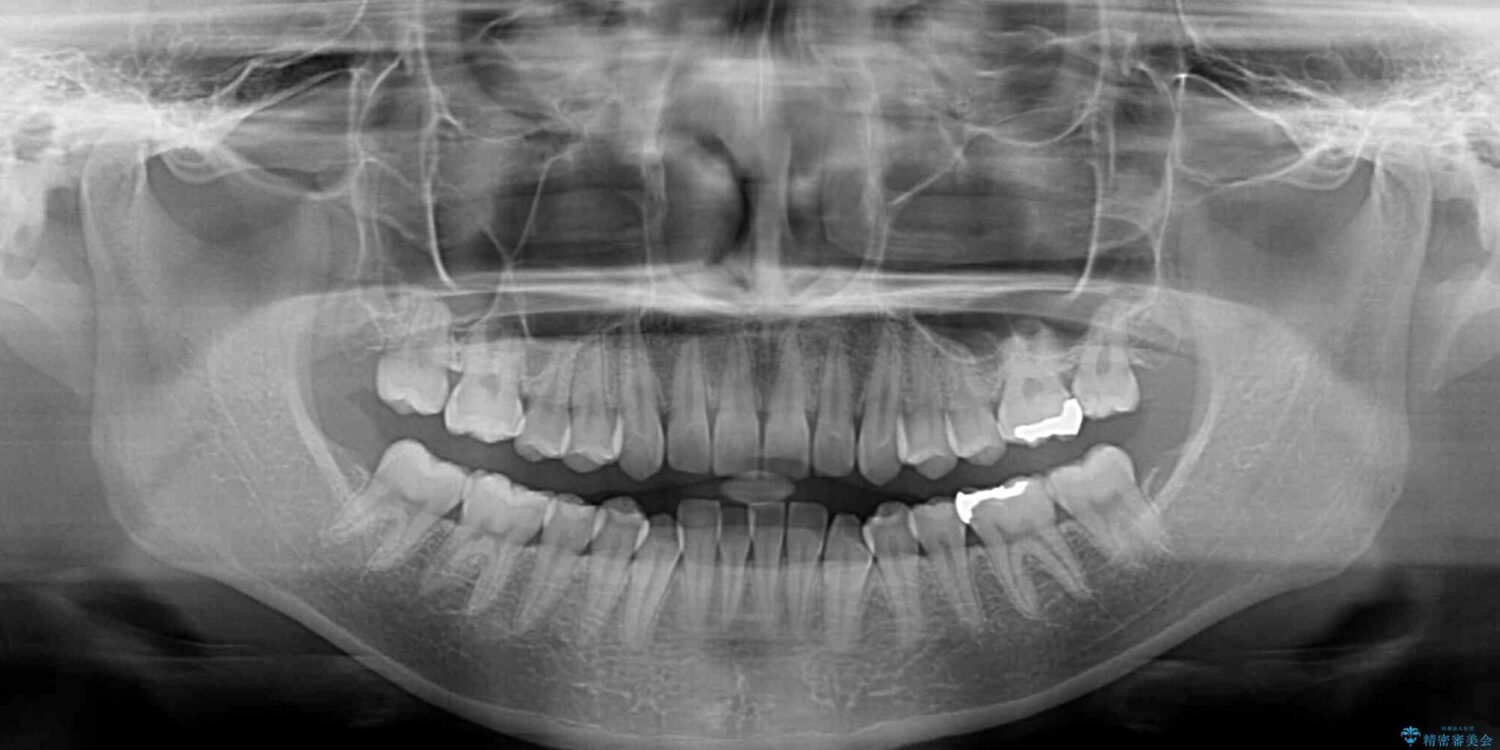

下顎の八重歯を気にして来院された患者様です。

下顎前歯にデコボコが集中していたため、顎間ゴムによる後方移動とIPR(歯と歯の間を削ること)により歯列を整えることとしました。

治療前、下顎前歯のデコボコが集中しており、奥歯の咬み合わせは、上顎に対して下顎が前方位にある状態でした。下顎の歯列を後方へ移動させる治療はインビザラインの得意とするところですので、1年程度で無事に治療を終えることができました。

治療前

• 【モニター】下顎前歯のデコボコをインビザラインできれいに 治療前画像